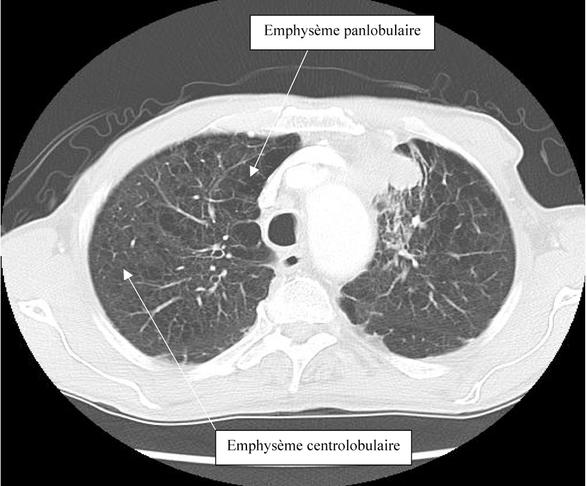

Trois types d’emphysèmes sont anatomiquement reconnus : 1) centrolobulaire ; 2) paraseptal et 3) panlobulaire. L’emphysème centrolobulaire est le plus fréquemment retrouvé, plus souvent dans les parties supérieures des poumons, et correspond à la destruction des bronchioles respiratoires et des canaux alvéolaires proximaux (figure 1). Il est souvent associé à une altération fonctionnelle plus marquée que la forme paraseptale (figure 2). Cette dernière affecte classiquement la périphérie des acini, s’observe donc plus volontiers en localisation sous-pleurale et est habituellement focale. L’emphysème panlobulaire (ou panacinaire) est retrouvé classiquement dans le déficit en α1-antitrypsine mais aussi dans des cas sévères sans anomalie génétique identifiable. Le lobule est diffusément affecté et l’atteinte est typiquement plus marquée au niveau des lobes inférieurs.3

Emphysème panlobulaire et centrolobulaire